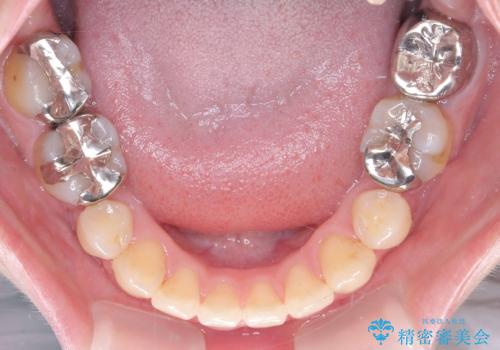

- 開咬と歯のデコボコ(叢生)、八重歯を主訴にご来院された患者様です。

矯正の精密検査の結果、上顎左右4番および下顎左右5番の計4本を抜歯し、ワイヤー矯正(クリア装置)にて治療を行いました。

虫歯があったので、虫歯治療は矯正前に行っています。